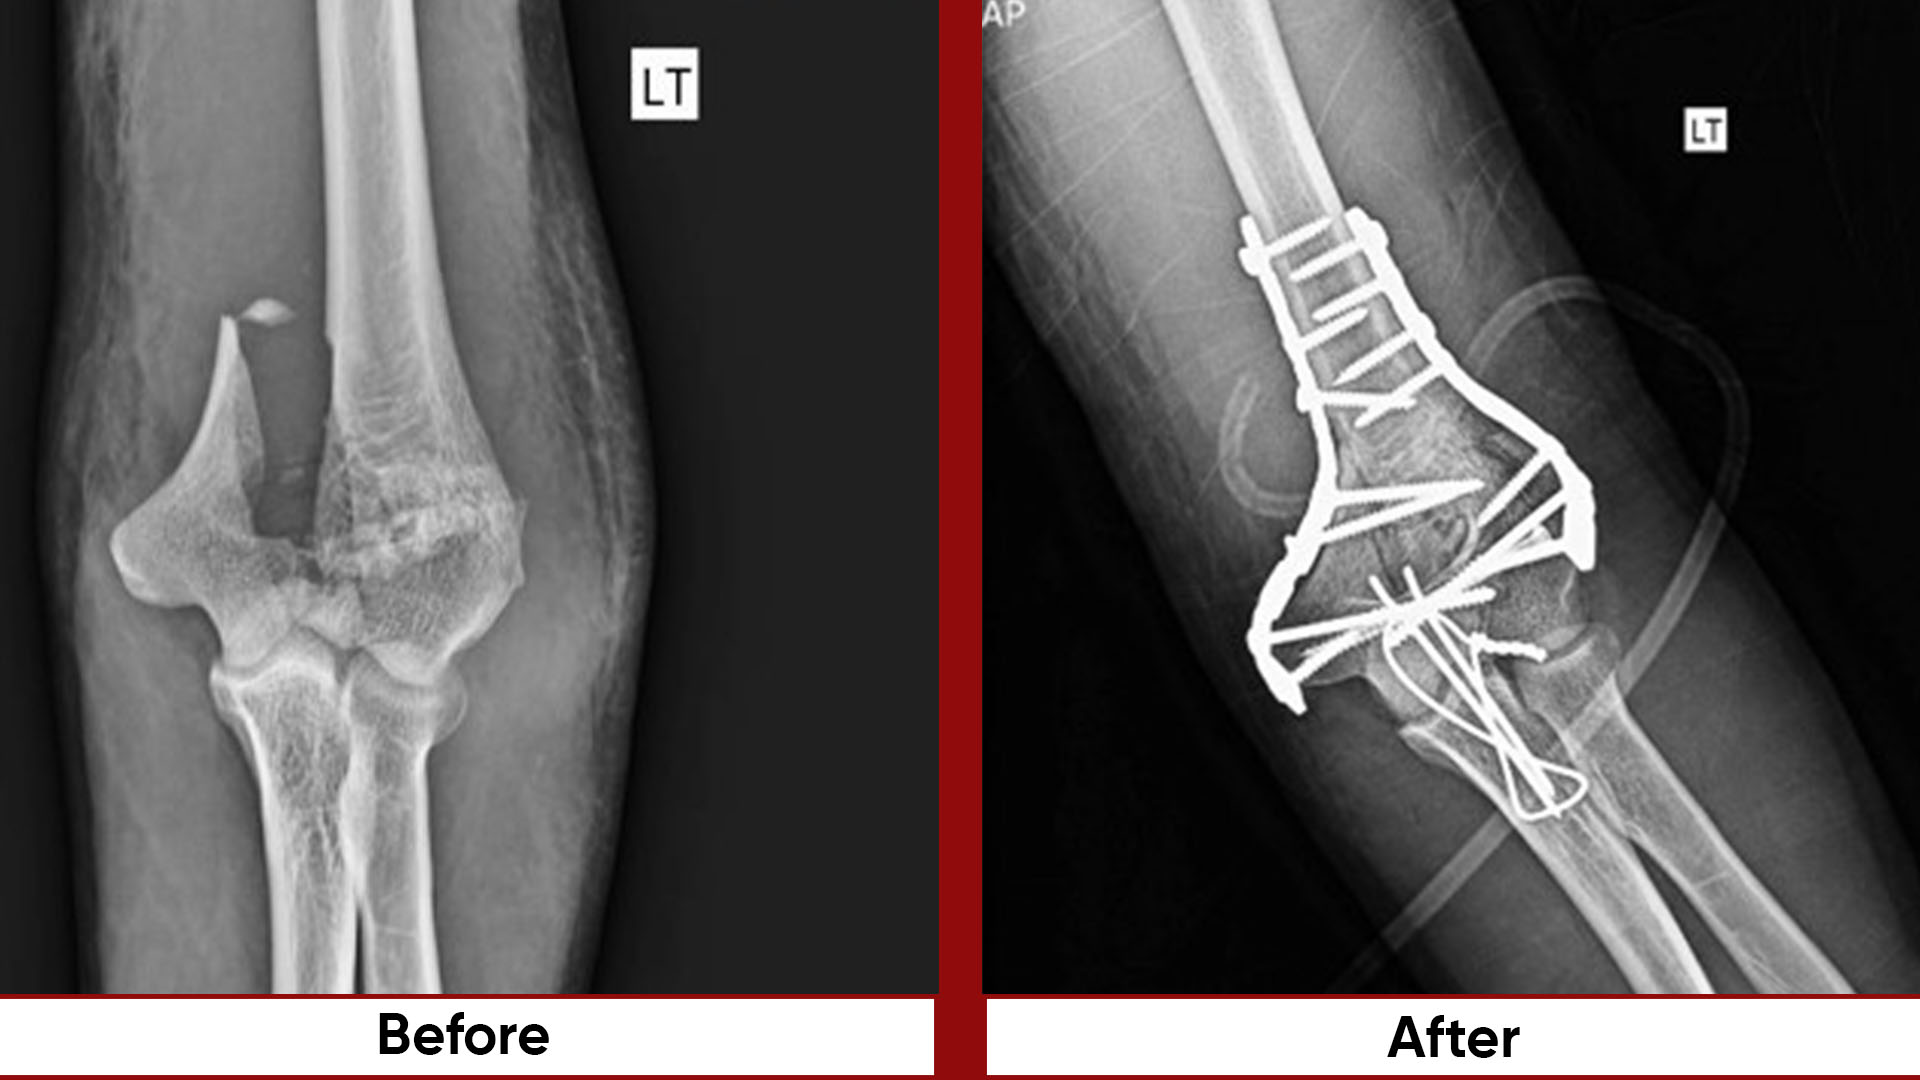

• Fracture Management (simple and complex trauma)

• Hand and Microsurgery